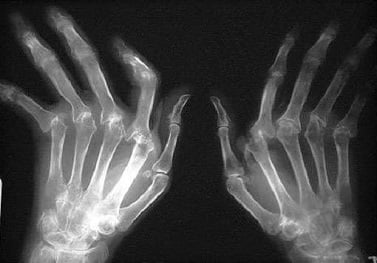

- Характерные рентгенологические изменения.

Основополагающее значение для диагностики ревматоидного артрита имеет рентгенография суставов, как правило, суставов кистей и стоп. Сужение суставных щелей, а также признаки разрушения участков костей, прилегающих к суставу, говорит в пользу ревматоидного артрита.